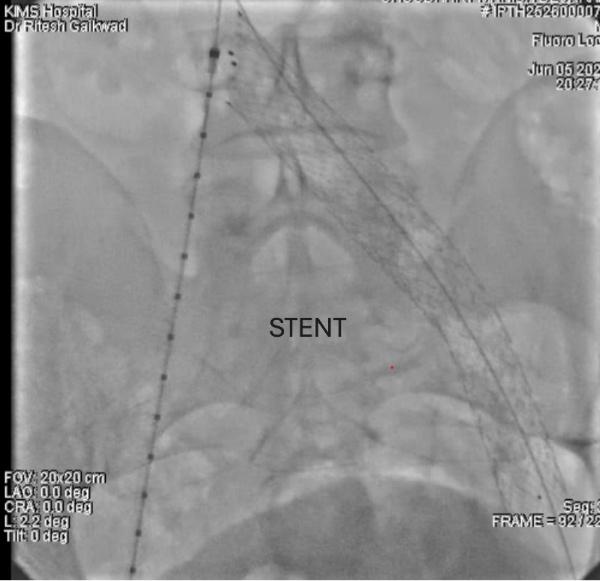

The patient underwent balloon angioplasty followed by deployment of a dedicated self-expanding venous stent in the compressed segment of the left iliac vein. The procedure was uneventful, completed in under an hour, and the patient was mobilized within two hours postoperatively.

The immediate postoperative period was remarkable. By the next day, he reported over 90% reduction in swelling and pain. Patient was discharged with rapid wound healing already underway — a dramatic turnaround after years of ineffective treatment.